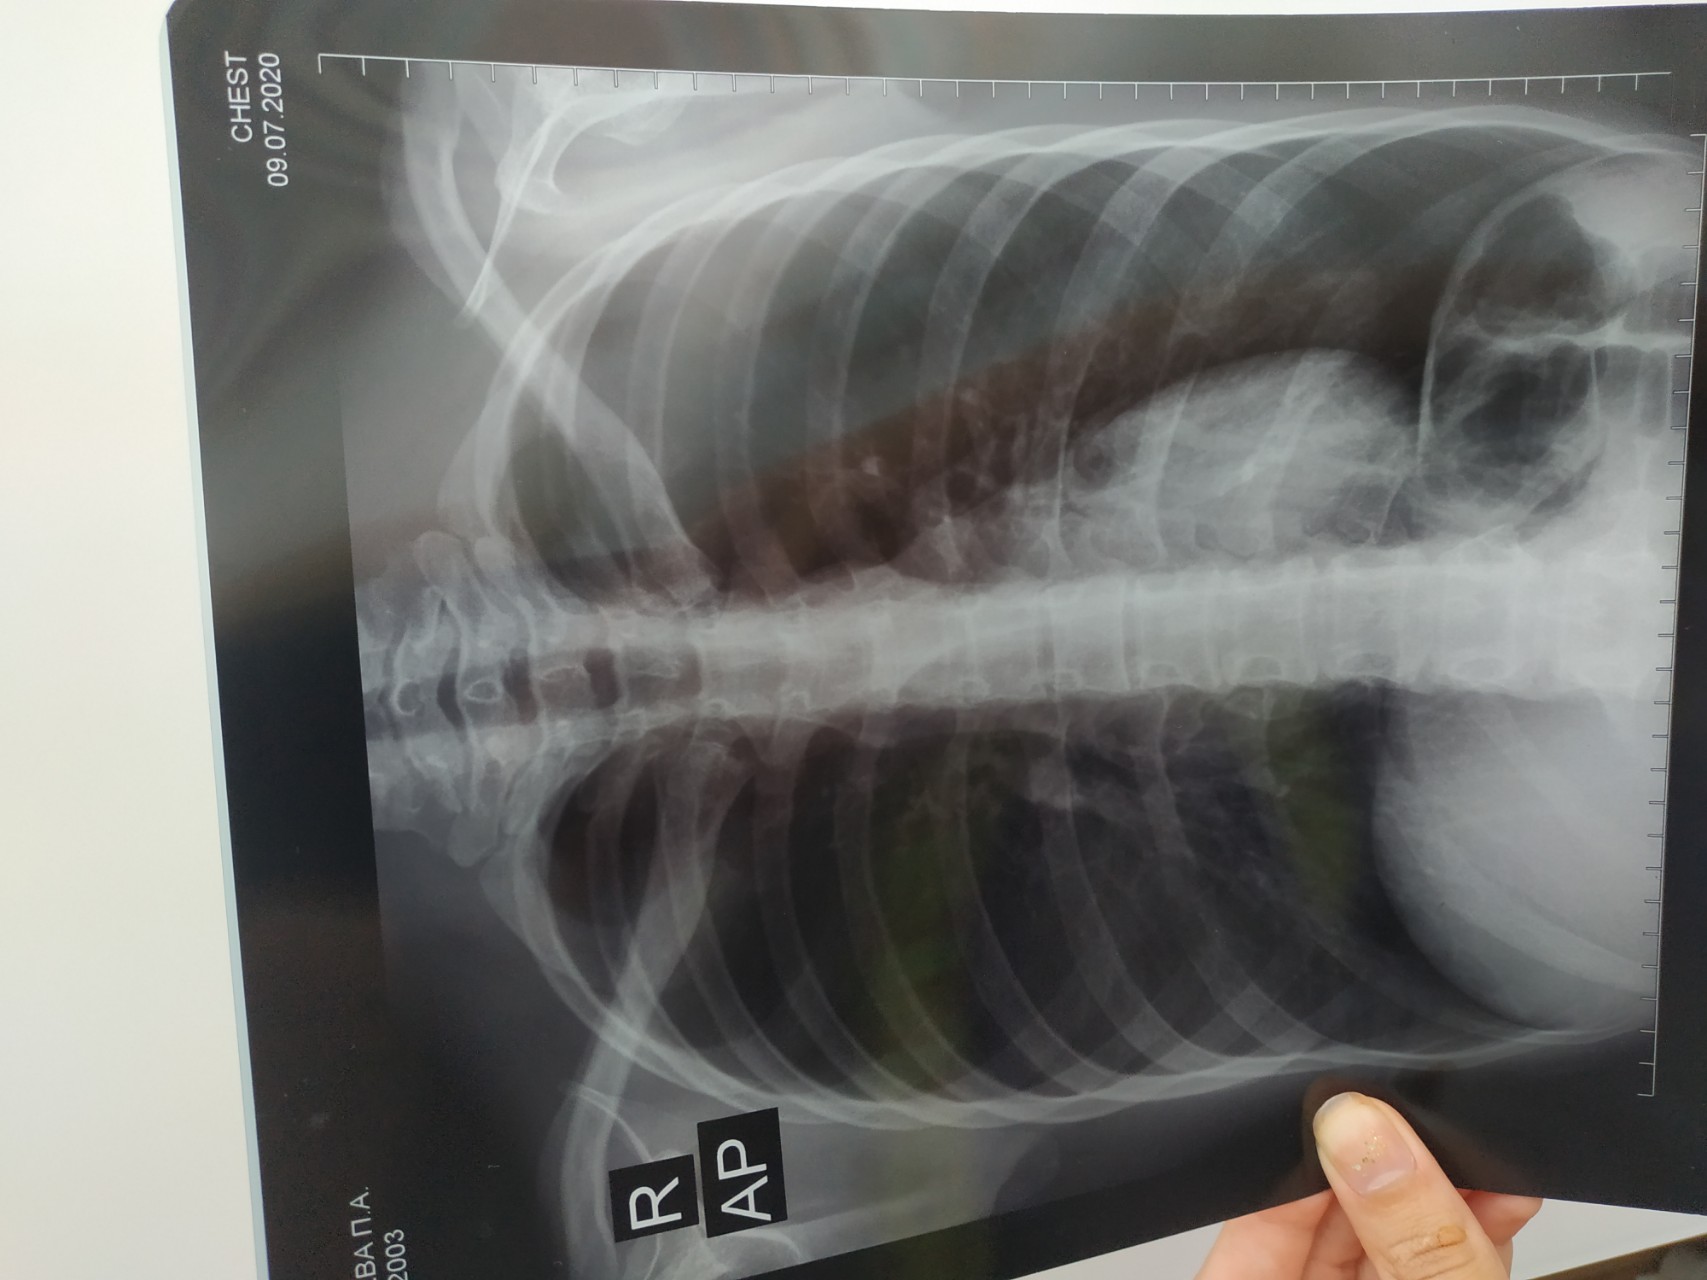

Нормальная рентгенограмма легких: что нужно знать